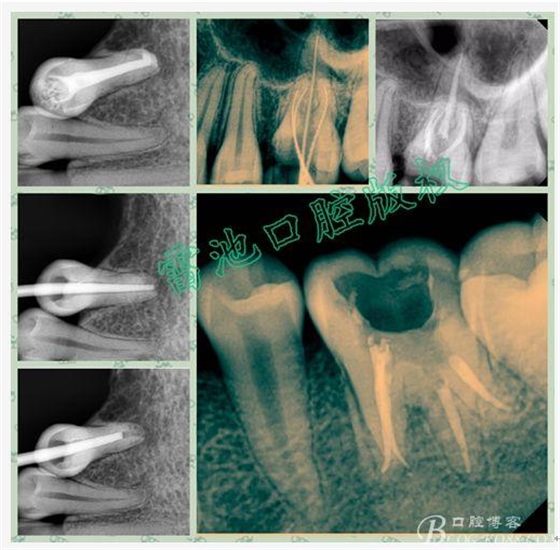

E、X線影像學的檢查研判能力:這點不需要強調(diào)太多,對于普通的非CBCT的二維影像對醫(yī)生讀片能力有一定的要求,有個逐步提高的過程,非一蹴而就,需要學會把二維的X線影像與三維的解剖結(jié)構(gòu)進行良好的對應結(jié)合,對于某些鈣化的髓室底,應通過想象把根管口的分布、根管的走向以及各種變化通過想象投射到對應的髓室底上;

1、查閱各種文獻,MB2的發(fā)生率在52-96%之間,治療時遺漏是上頜磨牙根管治療失敗的主因,2、一般位于MB1根管口與腭根管口方向的0.5-5mm范圍內(nèi),而大多數(shù)都位于MB舌側(cè)的1-3mm處,其中2mm以內(nèi)占85.7%,3、MB1-P根管口連線與MB1-MB2根管口的連線夾角大部分(74.3%)在30度以內(nèi);4、MB2的尋找大部分需要去除相應部位的牙本質(zhì);5、當找到的MB根管口呈“長線型”且有深色凹線向舌側(cè),或者找到的MB根管口明顯偏頰多提示有MB2的可能;6、DOM(牙科手術(shù)顯微鏡)的使用有助于找尋MB2;

F、其它找尋根管的特殊方法:包括染色法(使用赤藻紅或亞甲基藍染色后,通過聚合作用或冷光燈透照牙齒,并配合使用尖銳的根管口探針輕輕探查)、溝槽法(選擇合適超聲工作尖,在髓底懷疑根管口出現(xiàn)的特定位置切割一條淺溝,清洗吹干后通過放大設備觀察,一般溝底的牙髓組織呈白色,此法對找尋MB2非常有效)、以及發(fā)泡實驗等等。